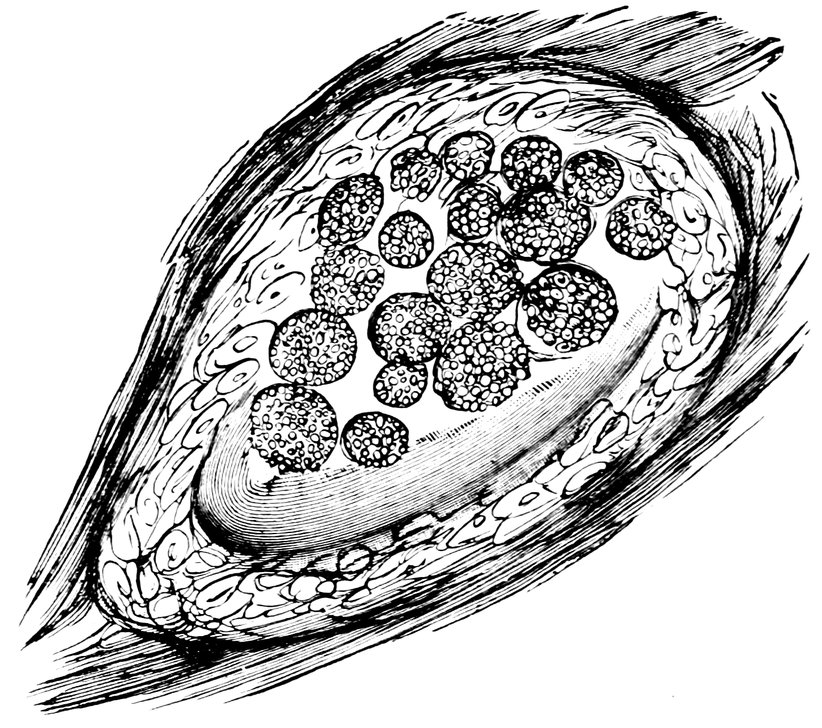

| 17. | Graafian follicles | 62 |

| 86. | Diagrammatic Representation of the Graafian Follicle | 585 |

We must first consider the changes in the ovaries, which play an etiologically important part. At the onset of puberty, the follicular masses of the ovary exhibit a more active growth, the follicles increase in size, with their contained ova they approach the surface, and finally, by the bursting of the follicles, the ova are extruded. Then, in the life-phase in which conception occurs, and under the influence of the hyperæmia of all the pelvic viscera that accompanies this process, a notable development of the corpus luteum takes place, this latter body reaching its maximum size in the eleventh week of pregnancy, subsequently undergoing involution and leading to the formation of a considerable scar. Finally, in the critical period of life in which the menstrual flow ceases, a continually increasing growth and new formation of connective tissue-stroma takes place in the ovaries at the expense of their cellular constituents, and a regressive metamorphosis of the graafian follicles occurs.